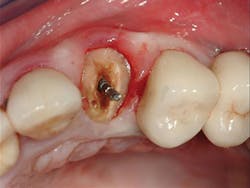

5. All tooth structure gone to the bone. Endodontic treatment. Post and core placed. Not enough tooth structure to provide a ferrule. Nonabusive occlusion (Figures 3 and 4)-Orthodontic tooth extrusion is a technique seldom used in dentistry, but it can possibly save such teeth. In spite of being taught to dental students, I find in my CE courses that orthodontic tooth extrusion is seldom accomplished. If the tooth root is long, the technique can be successful. Additional cost to the patient is necessary, accompanied by the time for orthodontic tooth movement, and a period of bone stabilization before restoring the tooth. Crown lengthening is another option if such treatment will not cause an esthetic challenge. Presence of abusive occlusion adds a strong negative to this clinical situation. Most dentists do not accomplish orthodontic extrusion or bony crown lengthening. Therefore, removal of the tooth and placement of an implant remain as the most predictable and viable solution.